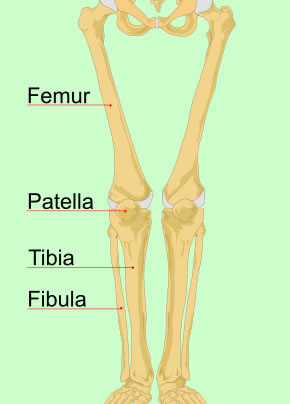

Image: Mariana Ruiz Villarreal - Leg Bones

All of the other authors agree that the knee can be luxated or sub-luxated to either side and backwards, but it "doth scarce admit of any Luxation forward, unless the cause be exceeding violent."2 Atkins says this is because of the position of the patella (knee cap) and the fact that it is difficult to bend forward far enough to displace. Paré explains that "the cavitie of the leg-bone [tibia] is superficiarie [superficial] and very smooth, but the cavitie of the lower end of the thigh-bone [femur] is made in the manner of a spout or gutter, & ...the head thereof is verie smooth and slipperie"3. He goes on to note that the joint is 'more lax' than the elbow and is therefore easier to dislocate. However, like Hippocrates, he says that it is easy to put back into place.